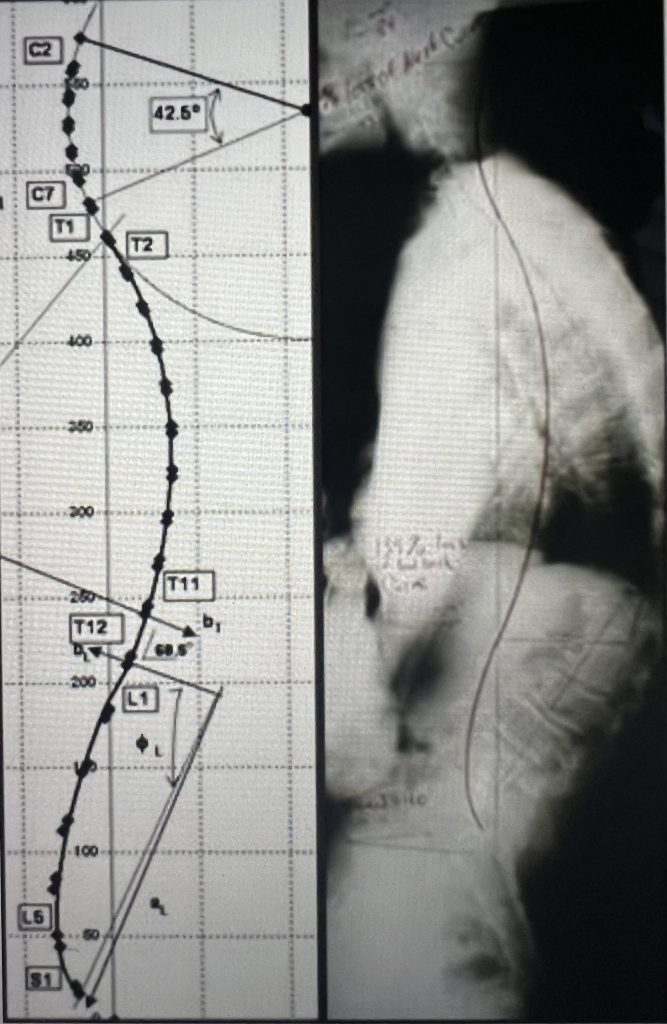

But this is not enough. Many people have good straight posture, but x-ray reveals they have a ramrod spine with none of the critical three curves for engineering stress- relief for the spinal cord. The second category of structural wellbeing lies in “Do we have the precise three curves for adequate spinal/functional health?” This lack of the proper three curves is a real problem for those where CBP chiropractic is unavailable.

At this time, idealspine.com will not sell CBP Denneroll spinal curve regainer products to unauthorized persons (non-chiropractors) for the legitimate reason that they cannot be used optimally without a CBP specialist analyzing the need and optimal placement for the postural improvement. We are hoping to nd some solution. Denneroll imitations can be found on the internet, but none of their effectiveness has been rigorously proven with pre and post xray as in the case of the Denneroll.